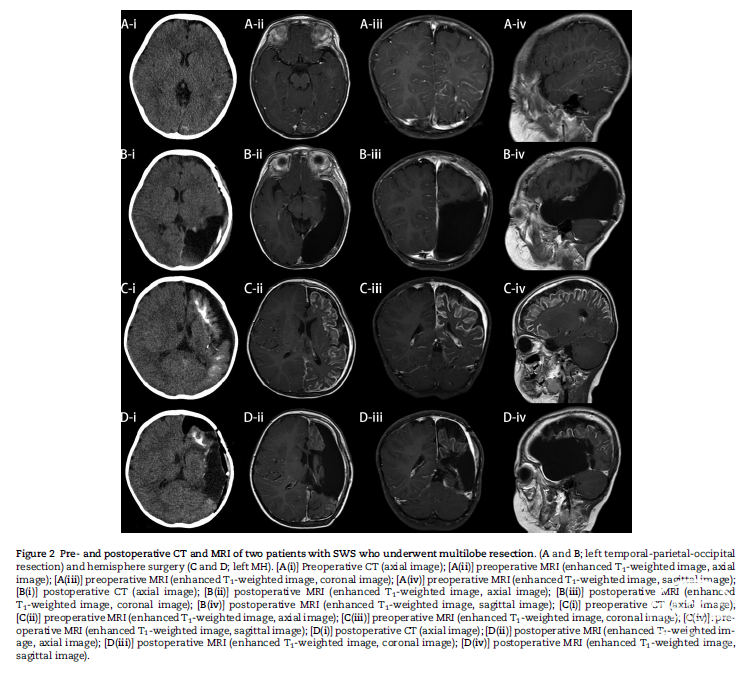

两种主要癫痫手术方式(局灶切除和半球手术)的术前和术后影像